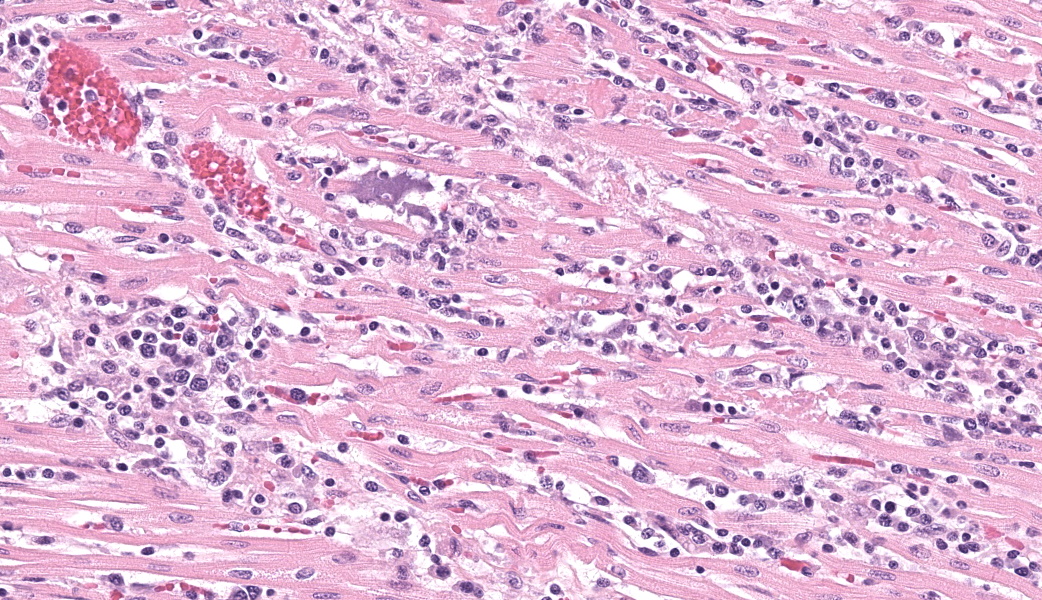

Expanding and infiltrating all layers of the heart, with the greatest severity in the myocardium, are large numbers of plasma cells, lymphocytes, and macrophages. Cardiomyocytes in areas of inflammation are multifocally hypereosinophilic, shrunken, and have striation loss with fragmented to absent nuclei (necrosis). There is mild, multifocal, interstitial fibrosis often associated with cardiomyocyte degeneration and inflammation. Throughout the myocardium, there are occasional cardiomyocytes that contain intrasarcoplasmic, variably sized (up to 100 μm in length) pseudocysts with numerous, 2-3 μm, round protozoal amastigotes.Contributor's Morphologic Diagnoses:

Heart: Severe, multifocal, chronic-active, lymphoplasmacytic and histiocytic pancarditis with intrasarcoplasmic pseudocysts containing amastigotesContributor's Comment:

T. cruzi can infect myocytes, endothelial cells, fibroblasts, and adipocytes, but has a tropism for cardiac muscle tissue.11 Grossly, there are no pathognomonic lesions for Chagas disease. Histologically, the cardiomyocytes will be expanded by a pseudocyst containing amastigotes. While best observed ultramicroscopically, the amastigotes will have a large nucleus and an adjacent rod-shaped kinetoplast, like Leishmania spp. Unlike the defined perpendicular orientation of the kinetoplast in Leishmania, the location of the kinetoplast relative to the nucleus changes during the life cycle and cannot be a diagnostic feature in Chagas disease.10 Unfortunately, additional diagnostics including PCR, culture, and serology were not performed so leishmaniasis cannot be completely ruled out, but the geographic and anatomic location of the organism along with the histologic appearance is most likely consistent with T. cruzi. Infection results in marked inflammation of the heart, often not associated with the intracellular pseudocysts. Myocarditis can lead to heart failure with cardiac arrest and potentially fatal arrhythmias. In this case, there was multi-organ evidence of heart failure including ascites (abdominal effusion) and centrilobular hepatocyte necrosis due to hypoxia.